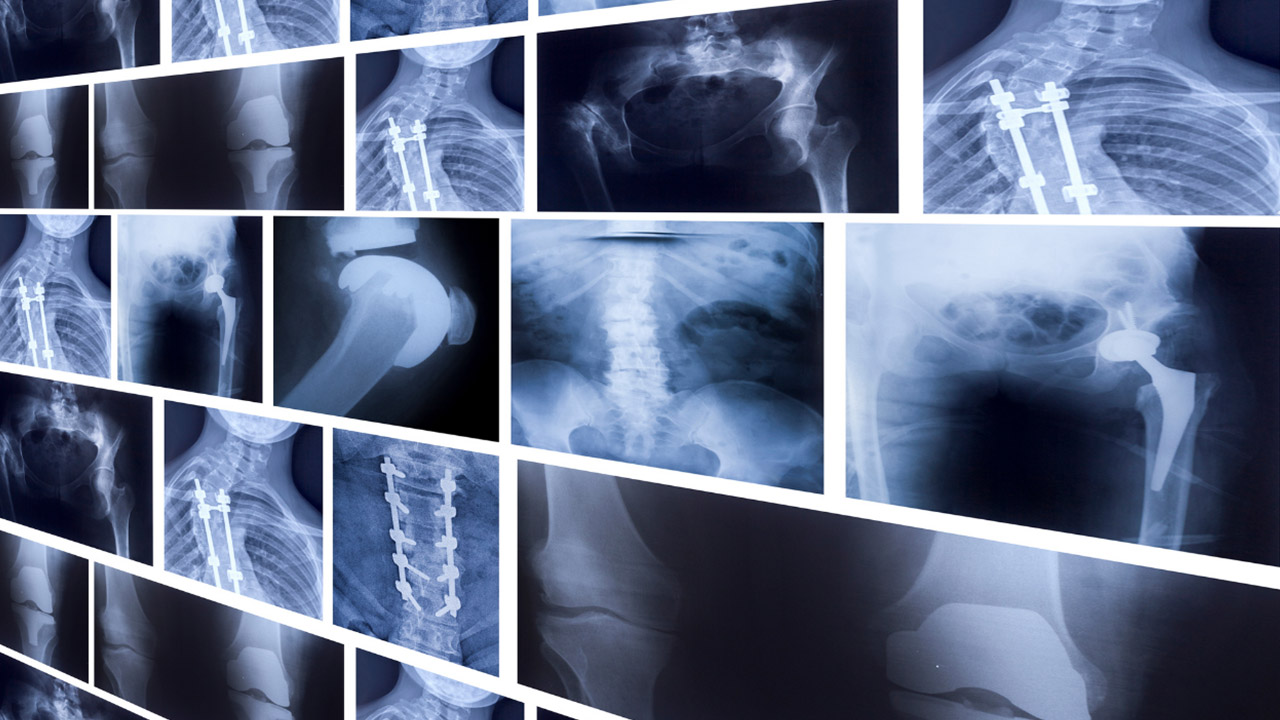

Cam Kemik Hastalığı, kemiklerin belirli bir travma veya yaralanma olmadan kırılmasına neden olan kalıtsal bir hastalıktır. İşte bu hastalıkla ilgili detaylar:

- Cam Kemik Hastalığı, kemiklerin hassaslaşarak kolayca kırılmasına yol açar. Genetik sebeplerle ortaya çıkar.

- Tedavi, hastanın durumuna bağlıdır. Fizyoterapi, cerrahi müdahale ve destekleyici tedaviler uygulanabilir.